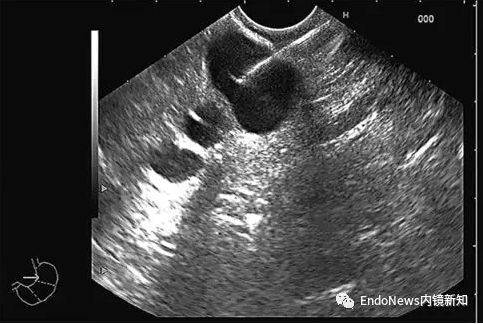

Computed tomography (CT), magnetic resonance imaging (MRI/MRCP), and cholangiography (MRI/MRCP) are accurate methods of detecting PCN, with MRI and MRCP being the most frequently used.

Although CEA and amylase or lipase improve the accuracy of endoscopic ultrasound (EUS) in differentiating mucous and non-mucous PCN, the diagnostic accuracy of these biomarkers is too low to determine the specific type of PCN.

EUS-FNA cytological sampling was performed for each cystic lesion.

Fluid analysis should include amylase or lipase, CEA, and cytology. Compared with EUS alone, cytological examination of EUS-FNA can improve the accuracy of differentiating mucilaginous and non-mucilaginous PCN and benign and malignant PCN. However, cytology in this case is highly specific but insensitive. (Histology EUS-FNB should be considered.)